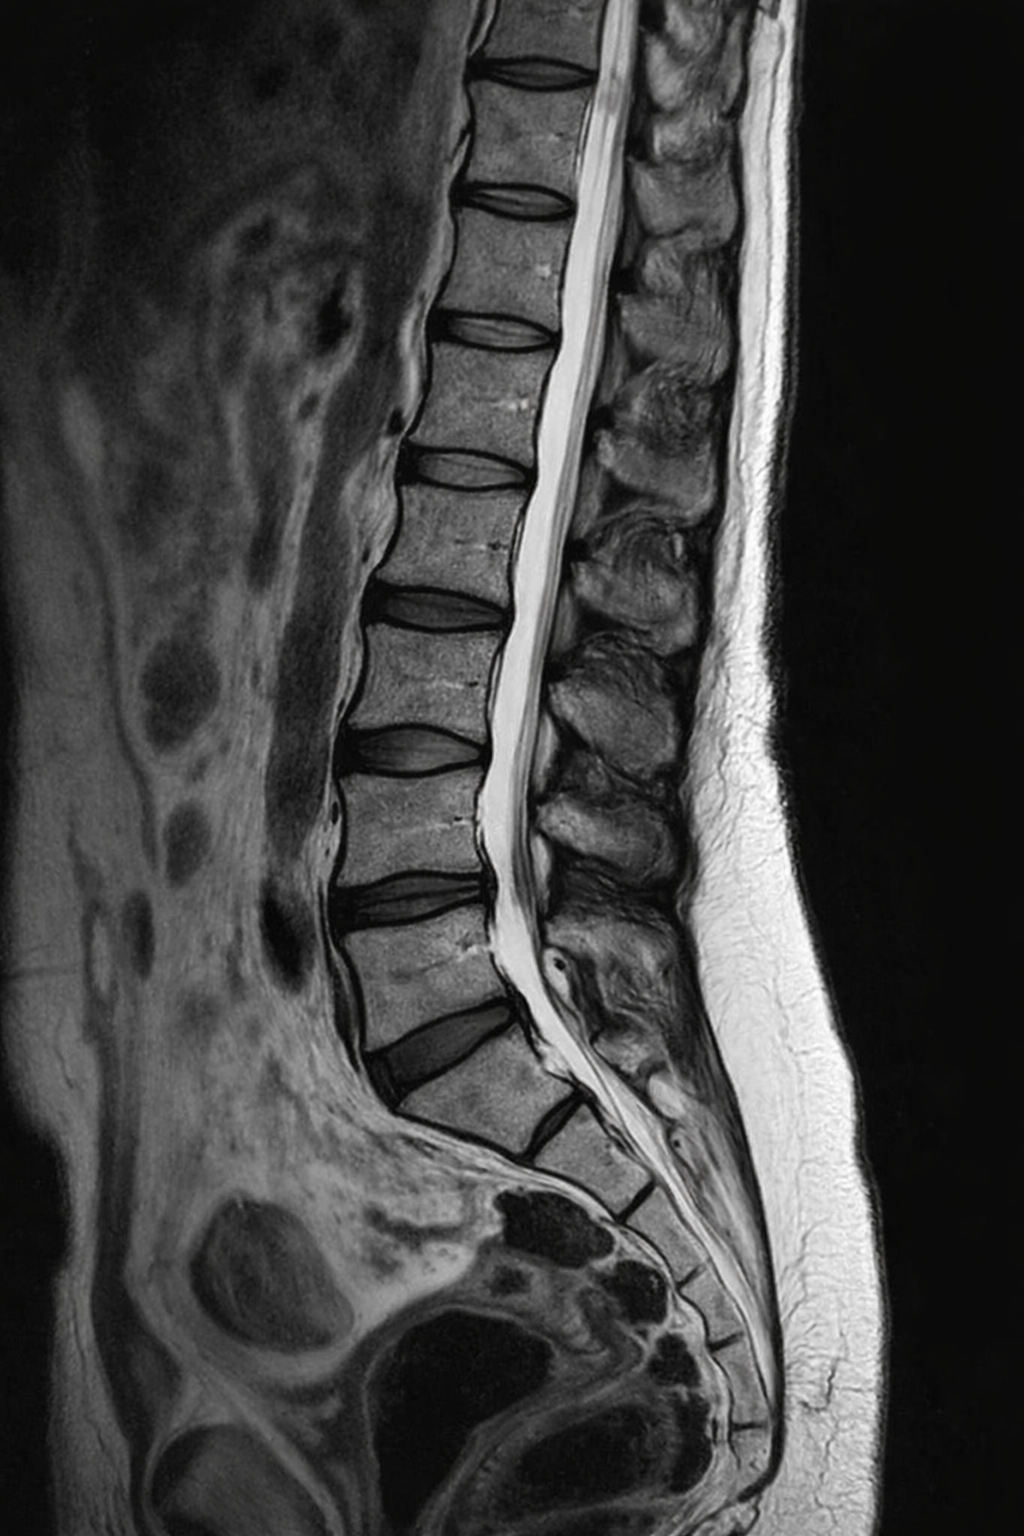

Du hast Bandscheibe? Ab ins MRT?

Es braucht für MRTs keine Einleitung - Keinen Humor - keine Erklärung. Du weisst was ein MRT ist. Hier ein paar harte Fakten die dir vielleicht neu sind:

Wir gehen jetzt nach und nach, Körperteil für Körperteil, ein paar Studien durch die im Zusammenhang mit MRTs gemacht wurden.

Rücken:

Lebensjahre Degenerative Prozesse Bandscheibenvorwölbung

Oha die Bandscheibe

Wie viele Menschen haben eigentlich Probleme mit den Bandscheiben?

Wenn du über 40 Jahre alt bist, hast du zu 50% mindestens eine Bandscheibenvorwölbung (Protrusion)

(Vgl. W. Brinjiki, P.H. Luetmer, B. Comstock et al. AJNR (American Journal of Neuroradiology) 2015)

Mit diesen Studien konnte Nachgewiesen werden, dass nicht jeder sichtbare Schaden im MRT zu Schmerzen führt. Im Gegenteil: Die meisten sichtbaren Schäden verlaufen entweder Beschwerdearm oder nur temporär Schmerzhaft.

Der Bandscheibenvorfall verändert sich so kurzfristig nicht. Schmerz ist flexibler als ein Bild.

Schmerz ist flexibler als eine Bandscheibe.